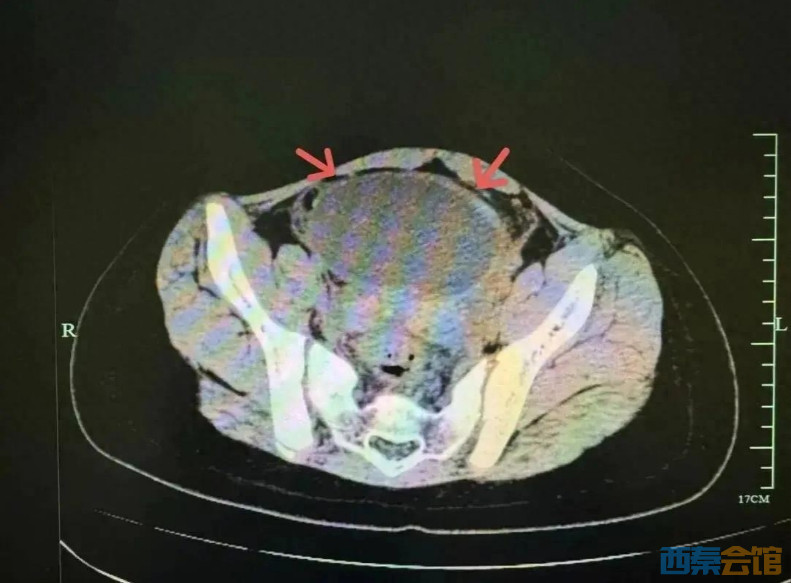

最近气温骤降,10岁的小吉突然闹起了肚子,又痛又吐,于是来到浙江省中西医结合医院儿科就诊,医生检查发现小吉血象高、B超提示肠系膜淋巴结肿大,类似儿童常见的急性胃肠炎及肠系膜淋巴结炎,医生进行了抗感染和对症治疗。治疗后小吉呕吐的情况好转了,但肚子还疼,复查感染指标反而更高了,医生立即进行了更深入的排查。